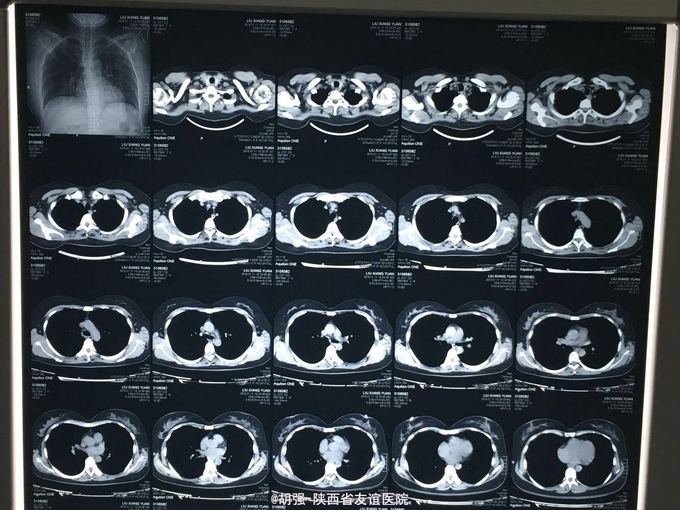

32岁女性患者,咳嗽、咳痰2周余 患者于两周前不明诱因出现咳嗽、咳痰,无胸痛咯血,无胸闷气短,无发热、寒战,自己服用头孢克肟1.0 2次/日及复方甘草合剂10ml3次/日治疗1周,效果不佳,遂来我院。 既往体检。

查体:两肺呼吸音粗糙,未闻及干湿性啰音及胸膜摩擦音。余查体无明显异常。 入院后查胸部CT无明显异常。血常规、肝肾功、血沉、结核抗体、心电图大致正常。T-sport试验及PPD试验 阴性。支气管镜检查:右肺中叶可见大量脓痰,吸痰送检。痰培养回报:肺炎链球菌。